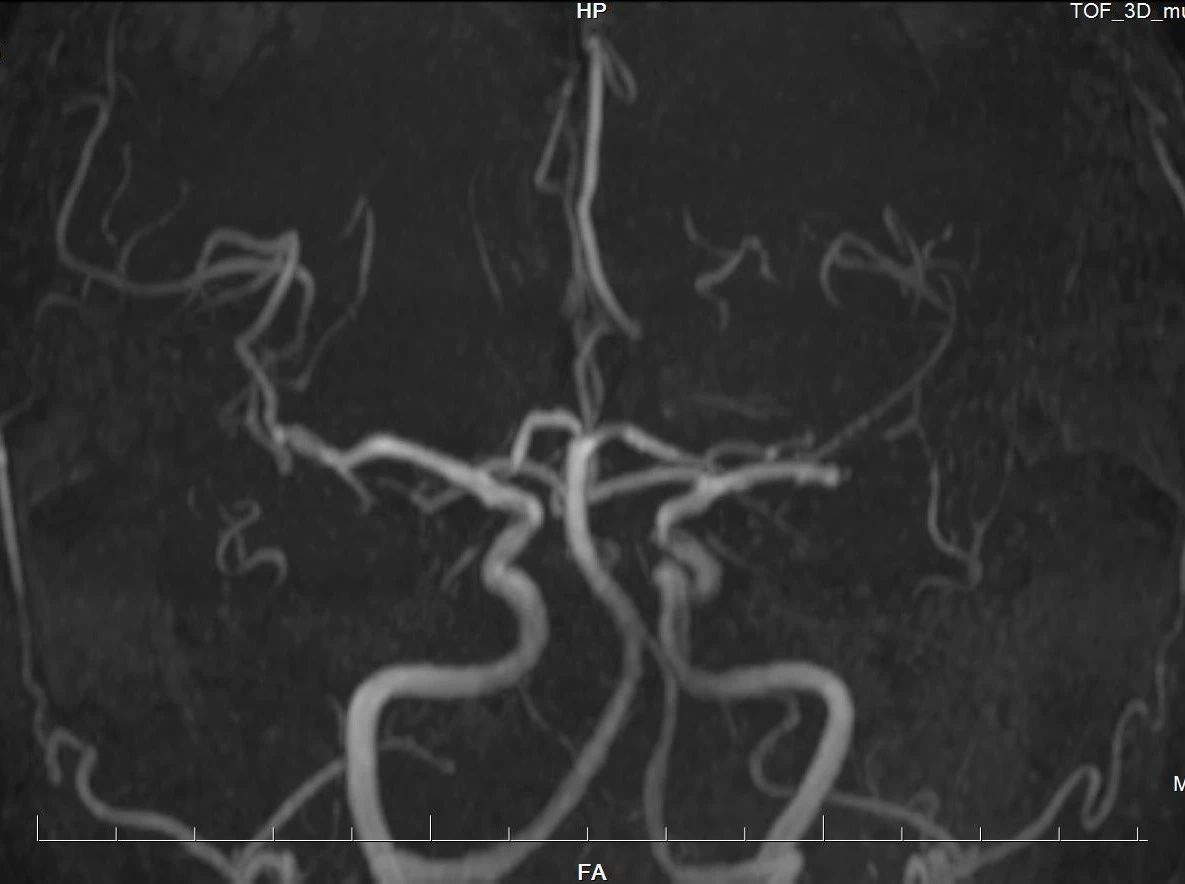

高场强设备(如3.0T MRI)提供更高分辨率的图像,能清晰显示血管狭窄、动脉瘤(≥3mm)、血管畸形等病变。研究显示,其对缺血性脑血管病的诊断灵敏度达95.2%,优于低剂量CTA。

一次检查可同时观察头颈部动脉主干及分支,结合平扫还能评估周围脑组织是否受损(如缺血灶),适合筛查脑卒中或复杂血管病变。